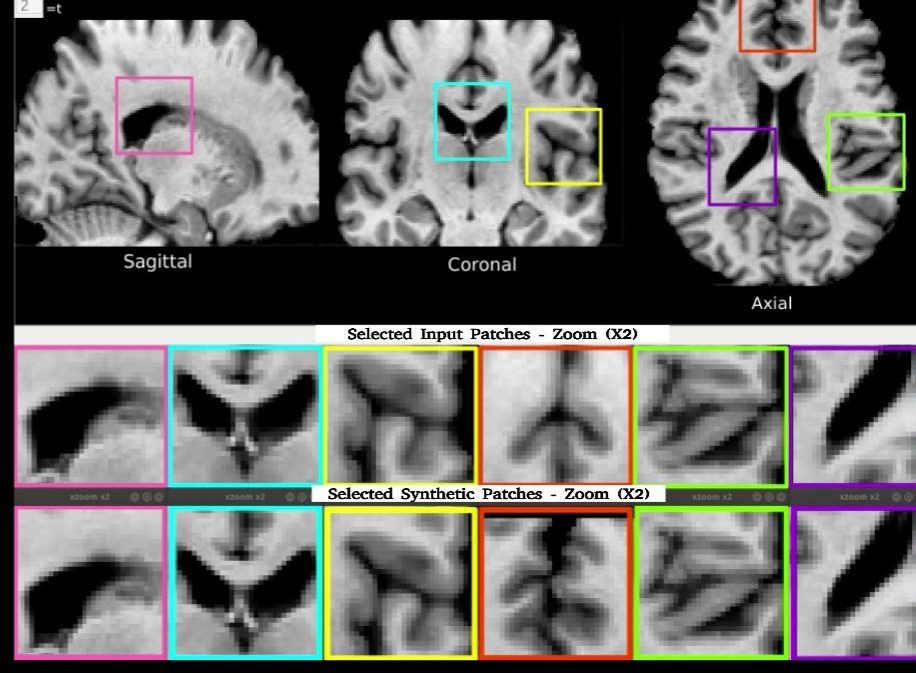

- DANI-Net/4D-DANI-Net: Reticoli avversariali in grado di generare realistiche simulazioni di progressione patologica cerebrale basate su MRI longitudinali.

- 4D-DANI-Net (MedIA 2022) Degenerative adversarial neuroimage nets for brain scan simulations: Application in ageing and dementiaAutori: Daniele Ravi, Stefano B Blumberg, Silvia Ingala, Frederik Barkhof, Daniel C Alexander, Neil P Oxtoby, Alzheimer’s Disease Neuroimaging Initiative